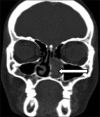

Nasal lobular capillary hemangioma is a rare benign tumor of the paranasal sinuses. This lesion is believed to grow rapidly in size over time. The exact etiopathogenesis is still a dilemma. We discuss a case of nasal lobular capillary hemangioma presenting with a history of epistaxis. Contrast enhanced computed tomography of paranasal sinuses revealed an intensely enhancing soft-tissue mass in the left nasal cavity and left middle and inferior meati with no obvious bony remodeling or destruction. We present imaging and pathologic features of nasal lobular capillary hemangioma and differentiate it from other entities like nasal angiofibroma.